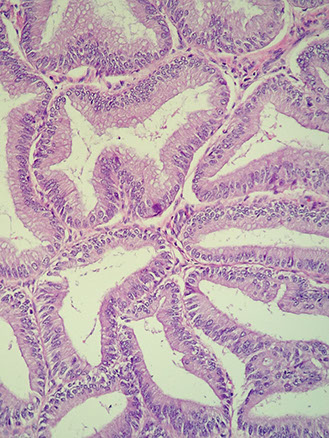

Villoglandular differentiation

Micro: papillae lined by columnar cells c bland oval nuclei

- may be assoc c inc rate of lymphovascular invasion and LN mets

Endometrioid carcinoma, FIGO grade 1

Histology and immunohistochemistry of endometrial endometrioid carcinoma. Endometrial endometrioid carcinoma shows a glandular growth pattern (A and B), a wild-type p53 expression (C), patchy p16 staining (D), diffuse nuclear staining for estrogen receptor (E) and progesterone receptor (F), focal nuclear positivity for HNF-1b (G), and negativity for napsin A (H) [3].